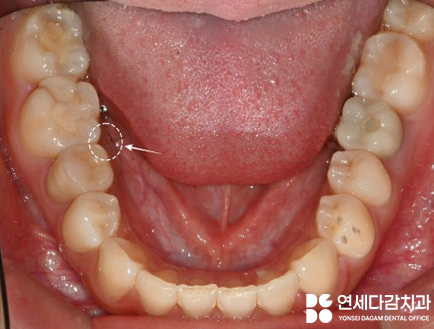

아래 사진은 술 후 8개월이 지난 시점 에서

촬영한 연세다감치과 구강 사진으로,

2024.08.19

역시나 잇몸이 잘 아문 것을 확인할 수 있습니다.

*추후 위치 상 관리가 어렵던

오른쪽 위 아래 사랑니(#18,48번)도

함께 뽑았습니다.